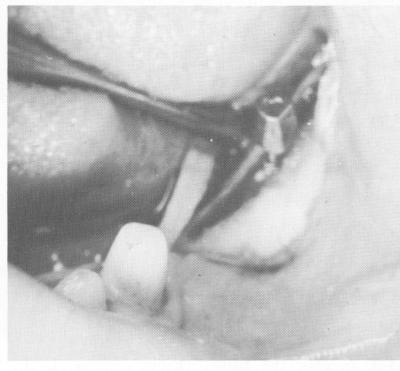

Fig. 11-11. The site is closed with simple surgical ties.

3 Oral bladevent placed & site closed with simple surgical ties